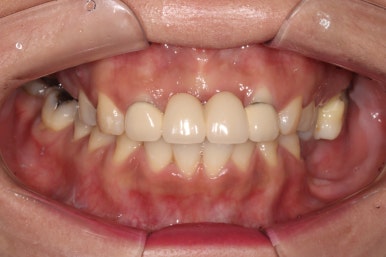

기다리는 동안 깔끔한 인상을 위하여 앞니 지르코니아 브릿지 치료를 해드렸어요.

왼쪽위 처음 내원하셨을 당시, 오른쪽이 앞니 지르코니아 완성 후 정면 사진입니다.

아직 어금니는 완성되지 않았지만..!...

보시면 파란색 화살표로 표시된 두 측절치에 기존에 치료받으셨던 PFM 브릿지의 경계가 드러나 회색 라인이 생기신 것을 보실 수 있고, 잇몸이 올라가버려 비교적 비 심미적인 모습인 것을 확인하실 수 있습니다.

지르코니아 브릿지로 교체함으로써 예쁜 첫인상을 완성해드렸어요.

이렇게 치료 중간에 환자분과 상의하면서 치아 색상을 적절히 채득해놓기에 가능한 일입니다.

본 환자분 같은 경우에는 자연스러운 치아 색상을 원하셔서 따뜻한 느낌의 색상으로 완성하였는데, 경우에 따라 보다 밝은 색상으로의 변화도 가능합니다! 연예인 라미네이트처럼요.